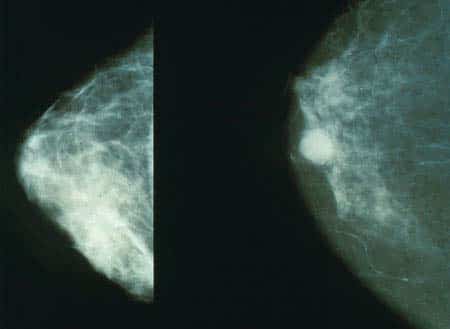

The breasts are paired structures located on the anterior thoracic wall, in the pectoral region. They are present in both males and females, yet are more prominent in females following puberty. In females, the breasts contain the mammary glands – an accessory gland of the female reproductive system. The mammary glands are the key structures involved in lactation. In this article, we shall look at the anatomy of the breasts – their structure, innervation, vascular supply and any clinical relevance. Note: This article will consider the structure of the breasts in the female. Pro Feature - 3D Model You've Discovered a Pro Feature Access our 3D Model Library Explore, cut, dissect, annotate and manipulate our 3D models to visualise anatomy in a dynamic, interactive way. Learn More Surface Anatomy The breast is located on the anterior thoracic wall. It extends horizontally from the lateral border of the sternum to the mid-axillary line. Vertically, it spans between the 2nd and 6th costal cartilages. It lies superficially to the pectoralis major and serratus anterior muscles. The breast can be considered to be composed of two regions: Circular body – largest and most prominent part of the breast. Axillary tail – smaller part, runs along the inferior lateral edge of the pectoralis major towards the axillary fossa. At the centre of the breast is the nipple, composed mostly of smooth muscle fibres. Surrounding the nipple is a pigmented area of skin termed the areolae. There are numerous sebaceous glands within the areolae – these enlarge during pregnancy, secreting an oily substance that acts as a protective lubricant for the nipple. By Ralf Roletschek [CC-BY-SA-3.0], via Wikimedia Commons Fig 1The surface anatomy of the breast. Note that the axillary tail has not been labelled in this diagram. Anatomical Structure The breast is composed of mammary glands surrounded by a connective tissue stroma. Mammary Glands The mammary glands are modified sweat glands. They consist of a series of ducts and secretory lobules (15-20). Each lobule consists of many alveoli drained by a single lactiferous duct. These ducts converge at the nipple like spokes of a wheel. Connective Tissue Stroma The connective tissue stroma is a supporting structure which surrounds the mammary glands. It has a fibrous and a fatty component. The fibrous stroma condenses to form suspensory ligaments (of Cooper). These ligaments have two main functions: Attach and secure the breast to the dermis and underlying pectoral fascia. Separate the secretory lobules of the breast. Pectoral Fascia The base of the breast lies on the pectoral fascia – a flat sheet of connective tissue associated with the pectoralis major muscle. It acts as an attachment point for the suspensory ligaments. There is a layer of loose connective tissue between the breast and pectoral fascia – known as the retromammary space. This is a potential space, often used in reconstructive plastic surgery. By Patrick J. Lynch, medical illustrator [CC BY 3.0], via Wikimedia Commons Fig 2The internal structure of the breast Vasculature Arterial supply to the medial aspect of the breast is via the internal thoracic artery (also known as internal mammary artery) – a branch of the subclavian artery. The lateral part of the breast receives blood from four vessels: Lateral thoracic and thoracoacromial branches – originate from the axillary artery. Lateral mammary branches – originate from the posterior intercostal arteries (derived from the aorta). They supply the lateral aspect of the breast in the 2nd 3rd and 4th intercostal spaces. Mammary branch – originates from the anterior intercostal artery. The veins of the breast correspond with the arteries, draining into the axillary and internal thoracic veins. Lymphatics The lymphatic drainage of the breast is of great clinical importance due to its role in the metastasis of breast cancer cells. There are three groups of lymph nodes that receive lymph from breast tissue – the axillary nodes (75%), parasternal nodes (20%) and posterior intercostal nodes (5%). The skin of the breast also receives lymphatic drainage: Skin – drains to the axillary, inferior deep cervical and infraclavicular nodes. Nipple and areola – drains to the subareolar lymphatic plexus. By TeachMeSeries Ltd (2025) Fig 3The five groups of axillary lymphatic nodes. All groups drain into the apical nodes. Nerve Supply The breast is innervated by the anterior and lateral cutaneous branches of the 4th to 6th intercostal nerves. These nerves contain both sensory and autonomic nerve fibres (the autonomic fibres regulate smooth muscle and blood vessel tone). It should be noted that these nerves do not control the production and secretion of milk. This is regulated by the hormones prolactin and oxytocin, which are secreted from the pituitary gland. Clinical Relevance Breast Cancer Breast cancer is the most common type of cancer to be diagnosed within the UK. After lung cancer it has the second highest death rate due to cancer. It is more common in women than men. Common presentations associated with breast cancer are due to blockages of the lymphatic drainage. Excess lymph builds up in the subcutaneous tissue, resulting in clinical features such as nipple deviation and retraction, and prominent skin between small dimpled pores (peau d’orange). Larger dimples are generally caused by cancerous invasions and fibrosis. This causes traction of the suspensory ligaments, causing them to shorten. Metastasis commonly occurs through the lymph nodes. It is most likely to be the axillary lymph nodes that are involved. They become stony hard and fixed. Following this, the cancer can spread to distant places such as the liver, lungs, bones and ovary. To assess a suspected breast cancer a triple assessment is carried out. This involves clinical examination, imaging using a mammogram and ultrasound scan and finally a biopsy. The staging of breast cancer uses the I-IV system or the Tumour Node Metastasis (TNM) system. Surgical treatment with adjuvant radiotherapy is the recommended treatment option. The operation is local and aims to remove only the affected tissue area. Failing this it is considered that a mastectomy is the best option. Adjuvant chemotherapy is also known to improve survival rates. By TeachMeSeries Ltd (2025) Fig 4Mammogram. Left – normal breast appearance. Right – breast lesion, suspicious for malignancy. Do you think you’re ready? Take the quiz below Pro Feature - Quiz The Breasts Question 1 of 2 Submitting... Skip Next Rate question: You scored 0% Skipped: 0/2 1800 More Questions Available Upgrade to TeachMeAnatomy Pro Challenge yourself with over 1800 multiple-choice questions to reinforce learning Learn More Rate This Article